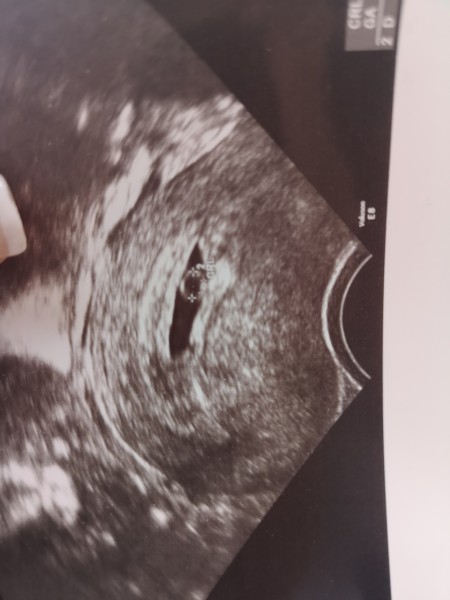

Perşembe ultrasonu (karnımdan)

image

Cumartesi gece vajinal ultrason